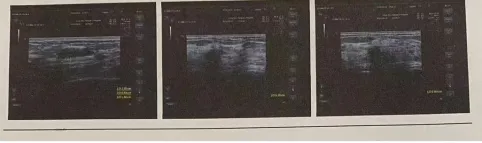

(治疗前后乳腺结节前后效果比对)

经过一个疗程(十次))的系统治疗,刘女士复诊时欣喜表示:乳房胀痛基本消失,自检结节明显软化、缩小,经期乳房胀痛也明显减轻,关节肿胀僵硬感大为减轻,晨僵时间缩短,畏寒乏力状况改善,整个人气色红润,精神焕发。“没想到中医调理这么全面,不仅治好了结节,连多年的关节炎都轻松了许多,姜主任真是妙手回春!”刘女士感激之情溢于言表。传承古训融现代,彰显中医独特优势      姜国良主任表示,此案例典型体现了中医在治疗此类慢性、复杂性疾病中的独特思路与优势:      整体观念,治病求本:不拘泥于“结节”或“关节炎”的局部病名,而是从整体机能失衡出发,探寻肝、脾、肾等多脏腑关联,通过调理内在环境,使痰瘀无以为生,痹阻得以疏通,从而达到异病同治的效果。      辨证论治,个体化方案:紧扣“阳虚寒凝”核心病机,治疗全程贯穿“温通”大法,针灸选穴与用药配方高度协同,完全因人施治。      绿色自然,副作用小:相较于西医手术切除或长期使用激素、抗风湿药物可能带来的创伤与肝肾损伤风险,中医外治内服相结合的方法更为安全温和,重在恢复人体自愈能力。守正创新,全面发展——康复理疗科的担当      烟台市北海医院康复理疗科在姜国良主任的带领下,始终坚持传承精华,守正创新的发展理念。科室不仅深入挖掘《黄帝内经》、《伤寒杂病论》等经典古训,熟练运用针灸、中药、推拿、艾灸、拔罐等传统技艺,还积极融合现代康复医学评估与治疗技术,形成了以中医特色为主、中西医结合的综合康复体系。      科室针对各类疼痛性疾病(如颈肩腰腿痛、关节炎)、功能失调性疾病(如乳腺增生、月经不调、失眠焦虑)、慢性病及术后康复等,均取得了显著疗效。此次刘女士的成功案例,再次彰显了科室在诊治多系统关联疾病方面的深厚功底与全面发展的学科实力。      姜国良主任强调,中医是博大精深的宝库,未来科室将继续深耕古典医学智慧,不断提升临床技艺,致力于为更多患者提供“简、便、验、廉”的优质中医药服务,让千年古法在现代医疗中焕发新的光彩,为健康烟台建设贡献中医力量。